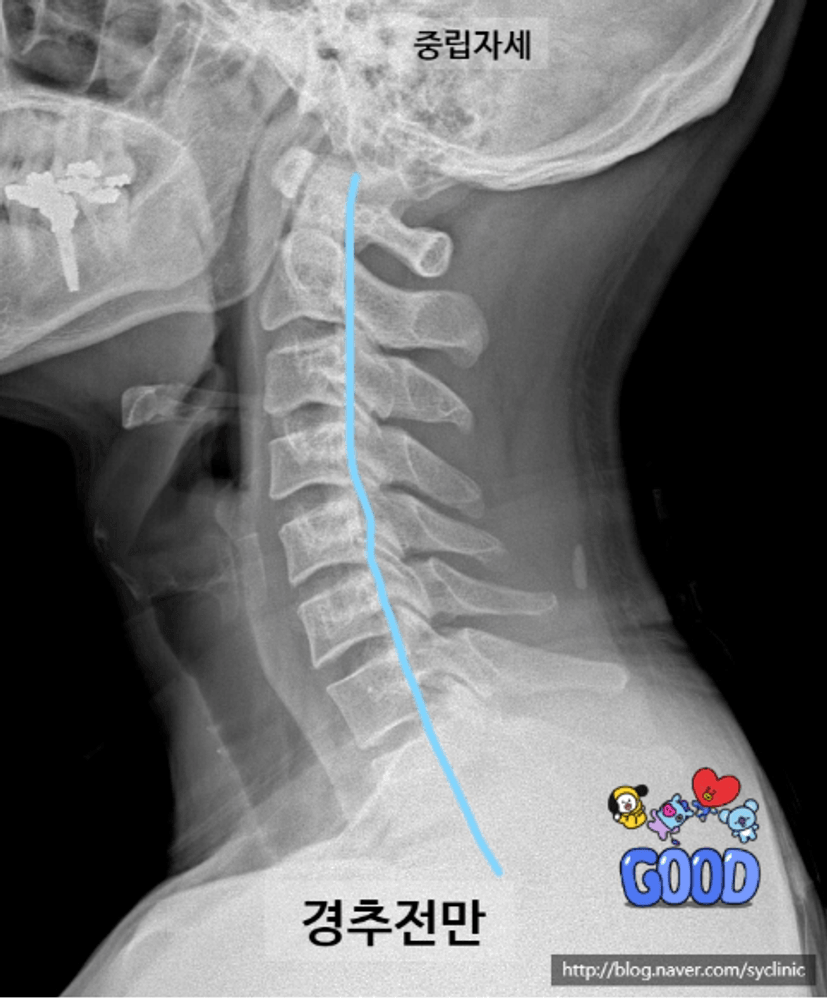

서 있는 사람을 왼쪽 옆에서 보면 요추와 경추가 앞으로 휘어진 C자 곡선을 만들고 있다. 이 곡선은 척추 건강에 엄청난 역할을 한다. 휘어진 상태를 전만이라고 하는데, 전만상태가 되면 일자상태에 비해 17배나 강해진다.

일자목이 되면 목의 움직임이 30퍼센트가량 줄어들고 목디스크에 걸리는 압력이 많게는 90퍼센트까지 증가된다. 일자목은 경추전만이 있는 목과 비교해 목 통증을 겪을 확률이 18배나 높다. (허리와 목을 의도적으로 세워야 한다. 이것이 척추위생운동이다. 전만자세는 목과 허리를 지키는 수호천사이다.

허리가 구부정해지면 목 디스크가 괴로워진다. 허리를 살리는 자세가 목을 살린다. 목과 허리의 경추전만을 유지하는 것이 무엇보다 중요하고 핵심이다!!

고정된 일자목은 일시적인 일자목 상태가 오래 지속되면서 목 디스크가 찢어진 채로 고정된 상태일 가능성이 높다. 엑스선 영상에서 확인되는 고정된 일자목은 목 디스크 병의 표현일 가능성이 높다. 또한 경추전만이 없어진 고정된 일자목 자체가 목 디스크 손상의 원인이 된다.